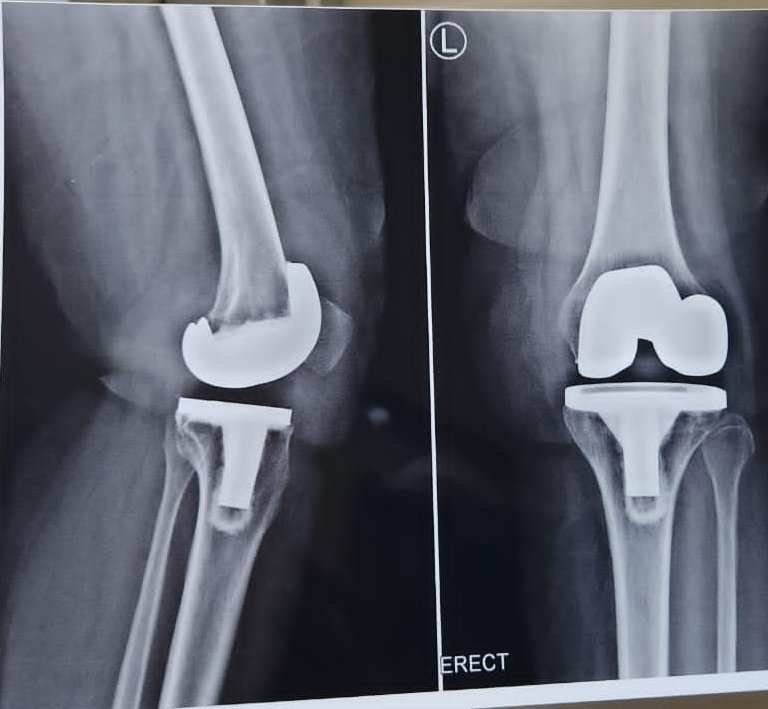

Hello #orthotwitter

55 y/o F, 3 mo post-op, pain with WB since 1 mo.

PMHx unremarkable, non-smoker. Pain constant, ↑ with ambulation, ↓ with rest, ↑ with flexion >90°

Neutrophils 72

ESR 45

CRP 10

PCT normal

Thoughts?

@kneedoclond @EdinburghKnee @aberizzi @drsebheaven